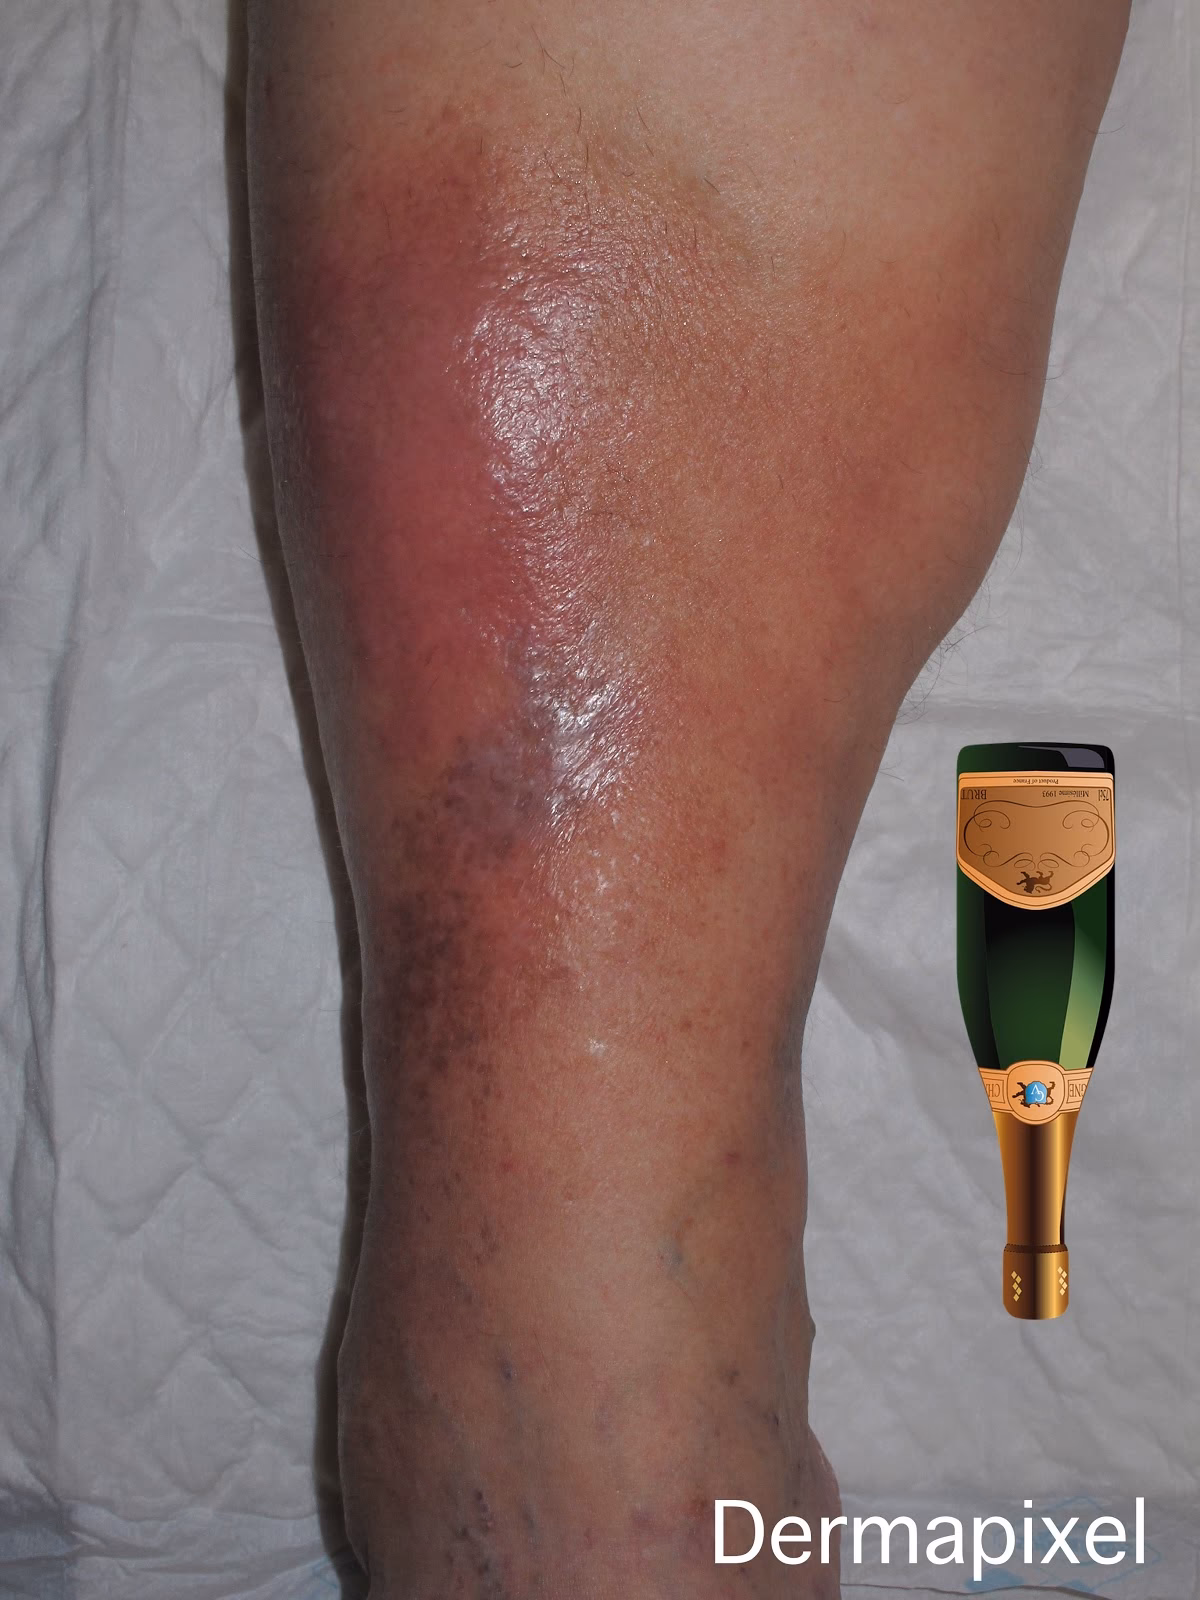

Esta fase se caracteriza por la aparición de una placa en la piel, generalmente en la parte inferior de la pierna. Esta placa es eritematosa (rojiza), indurada (dura al tacto), con una sensación de calor local y, muy importantemente, dolorosa. El dolor es, de hecho, uno de los síntomas principales y a menudo el motivo de consulta inicial.

La presentación en la fase aguda puede ser muy similar a la de una celulitis (una infección bacteriana de la piel), lo que explica la frecuente confusión diagnóstica. Esta fase puede durar desde un mes hasta un año, y a veces presenta cuadros recurrentes o “subintrantes”, donde los síntomas agudos reaparecen.

Clínicamente, esto se manifiesta como una induración persistente de la piel. Un signo característico de la fase crónica, especialmente en la parte inferior de la pierna, es lo que se conoce como el Signo de la Botella de Champagne Invertida. Esto describe la apariencia de la pierna, que se vuelve más estrecha en la parte inferior, justo por encima del tobillo, mientras que la parte superior puede permanecer más ancha, recordando la forma de una botella de champagne invertida.